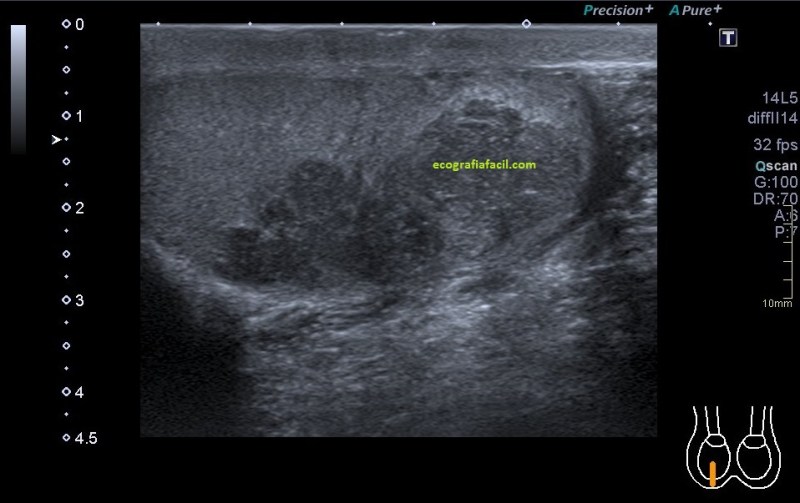

En algunas ocasiones podemos encontrarnos esto:

Compara la imagen 1 y la 2, grábala en tu memoria fotográfica. Ambas son unas imágenes en corte longitudinal del teste derecho de dos pacientes distintos.

Una vez que hemos encontrado la lesión, es momento de estudiarla detenidamente, su aspecto, tamaño bordes y vascularización son vitales para que la radióloga pueda efectuar un informe.

El aspecto de esta lesión, su semiología ya la has visto en estos dos casos diferentes, pero tienen en común, de modo general, hipoecogenicidad, heterogenicidad, bordes irregulares, con aspecto polilobulado y de tamaño y número variable.